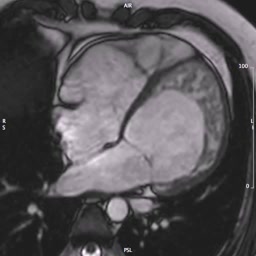

Le indicazioni e le controindicazioni alla RM cardiaca. Quando le informazioni fornite dalla TC sono fondamentali e quando superflue.

Trombosi endoventricolareAutore: Santo Dellegrottaglie

Categoria: Videoalbum

Parole chiave: diagnosi rm trombo -